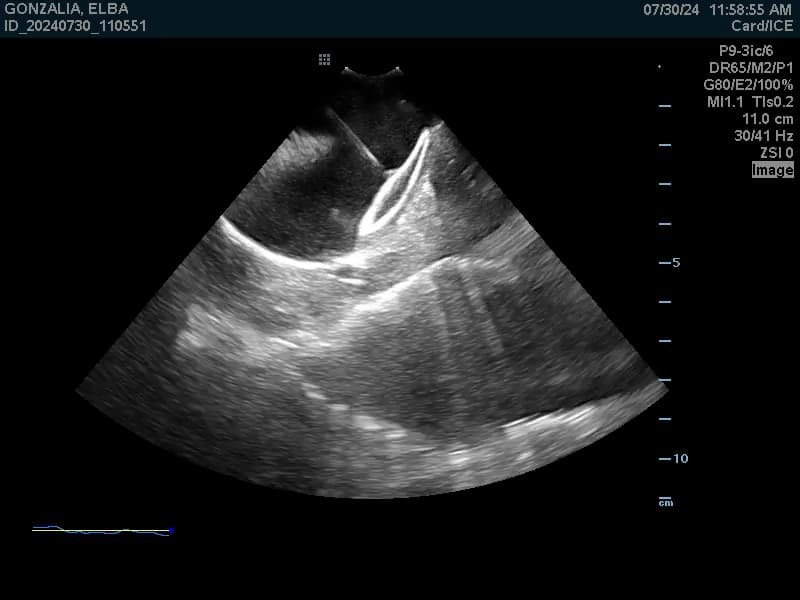

Cierre Percutaneo de Orejuela Izquierda

El procedimiento de Cierre de la Orejuela Izquierda es un tratamiento diseñado para reducir el riesgo de accidente cerebrovascular (ACV) en pacientes con Fibrilación Auricular (FA).

- ¿Qué es la Orejuela? Es un pequeño saco o apéndice muscular ubicado en la parte superior izquierda del corazón (la aurícula izquierda). Es una cavidad que no es esencial para la función normal del corazón.

- El Riesgo en FA: La Fibrilación Auricular es un latido irregular que hace que la sangre se «estanque» y se mueva lentamente dentro del corazón. Los estudios demuestran que, en pacientes con FA, alrededor del 90% de los coágulos de sangre que causan ACV se forman precisamente dentro de esta Orejuela.

- El Objetivo: El procedimiento busca sellar o cerrar la Orejuela para impedir que los coágulos que se formen allí puedan salir y viajar al cerebro.

La forma más común de realizar este cierre es mediante un procedimiento mínimamente invasivo:

Se realiza bajo anestesia general.

Se hace una pequeña punción (similar a un cateterismo) en una vena de la ingle (pierna).

Se introduce un catéter a través de la vena hasta llegar al corazón y la Orejuela Izquierda. A través del catéter, se despliega un dispositivo de cierre (que parece un pequeño paraguas o tapón) dentro de la Orejuela. Este dispositivo sella permanentemente la abertura de la Orejuela.